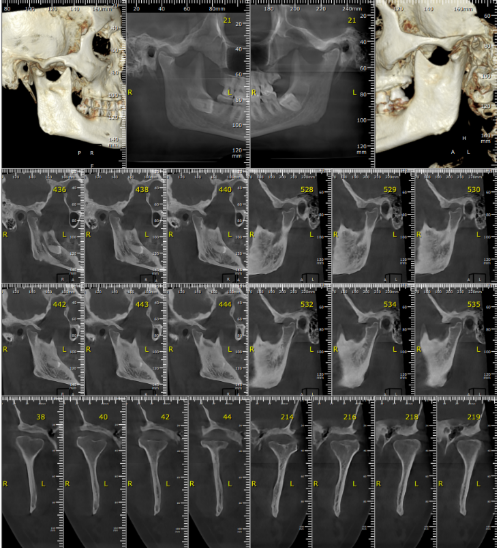

We ordered imaging, which confirmed the severity:

- Bilateral TMJ osteoarthritis

- Disc displacement without reduction

- Condylar bone loss

Despite her structural degeneration, Maha wasn’t ready for surgery — and we wanted to help her.

Image: X-ray showing TMJ degeneration

Imaging showed bilateral condylar damage and disc displacement without reduction.